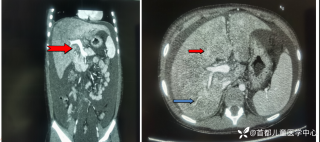

西地兰vip普外科医师

文/西地兰 特别声明:所有观点仅代表个人言论 特别声明:与当事双方均无利益相关 山东男孩,目前全网沸沸扬扬,看过一些观点,直言不讳地说,大多偏颇。要么一股脑地指责医方的全责,甚至有说千万别在县医院看病。要么又为医方无休止的遮羞,认为这样的手术在县医院做下来已经非常了不起。而我想到的是,以后面临类似的病例,我们怎么办?那么我们不如来一次专业的病案讨论。既然是事后讨论,难免有事后诸葛亮的感觉,但是假如下一次,同行们遭遇这样的病例,如何处置?这是医疗行业所面临的问题。希望我整理的这些思路和相关病例,对同行们有所帮助!就目前的资讯外界不足以判断是否需要急诊,如果需要急诊,那么只能根据术中所见进行处理,

目前知道的消息,第一,术前发现一个血肿,然后做增强CT发现一个占位,没说血肿与肿瘤的关系,术后病理没有描述肿瘤出现破裂出血,大概率就一个小血肿,我就不明白当地主任凭哪个指针去给这小孩开急诊刀的?哪个指南告诉他需要急诊开?第二,诊断不明确他想的不是进一步检查,一边观察一边进一步查,他反而选择腹腔镜探查,这个探查的指针在哪?第三,腹腔一个血肿,没有活动性出血,没有血压心率出现问题,为什么要开腹进去碰它?不能等血肿吸收再明确肿瘤性质吗?第四,1点进腹,3点病理结果出来,按这个时间还算顺利,应该还没出事,孩子还算平稳,病理是低度恶性,切了就治愈,他一年能开几台这手术,就敢继续做,拿孩子练手。第五,后面

2023年10月26日,来自山东菏泽市成武县的小烨和他家人的命运被彻底改变了。这个原本阳光、可爱的小男孩在一次意外被撞击后,在医院检查出了腹腔内存在肿瘤,并在手术中被切除了包括十二指肠、胰腺、大部分胃和小肠等多个器官。此后便无法再像正常人一样吃饭、喝水,活着要靠长期静脉注射营养液。一份2024年12月由第三方机构出具的司法鉴定意见书显示,当时给小烨做手术的成武县人民医院在该医疗行为中存在过错,与小烨的损害后果之间存在因果关系,建议医疗过错在损害后果中的原因力大小为同等原因。此外,另一份由成武县卫生健康局在2025年9月28日发出的书面答复中显示,成武县人民医院存在24小时内未完成病历;手术知情